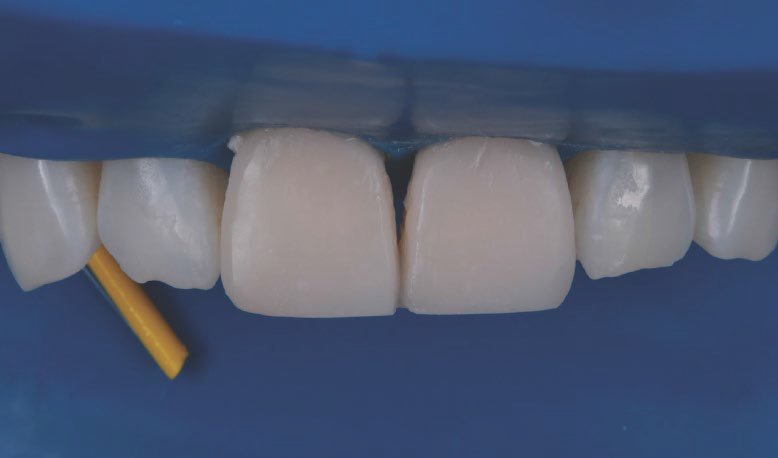

Placement of the second and final layer of 3M™ Filtek™ Universal Restorative A1 shade.

Restorations after polishing using the 3M™ Sof-Lex™ Diamond Polishing System.